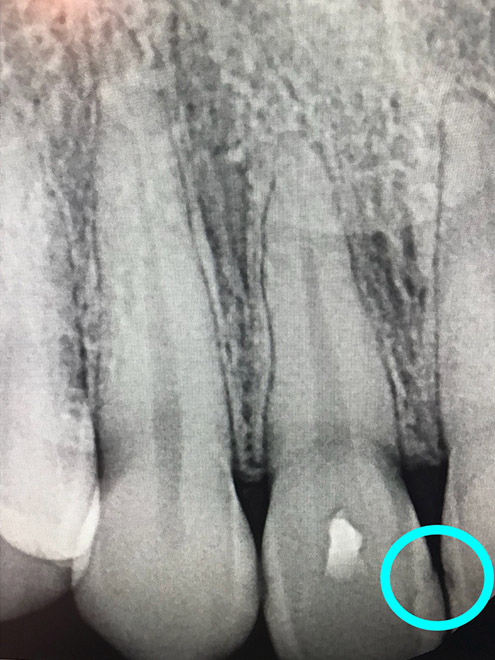

Bone healing with ozone treatment and SRP

Reverse Gum Disease: Bone Healing